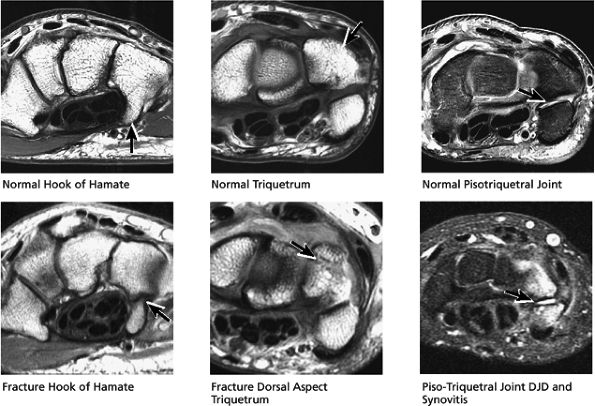

FIGURE 10.31 ● Normal coronal anatomy. (A) Fatty atrophy or denervation of the thenar muscles raises the possibility of median neuritis, and in such cases the median nerve is closely examined for enlargement or increased signal. (B) Tenosynovitis of the flexor tendons with fluid in the tendon sheaths can occasionally cause enough mass effect on the median nerve to cause median neuritis. (C) The first carpometacarpal joint (the articulation between the trapezium and the base of the first metacarpal) is a common location for degenerative arthrosis, often visualized at the corner of a coronal image. (D) Fluid in the pisotriquetral recess is a common finding. In the absence of other findings such as degenerative changes at the joint, a small amount of fluid in the pisotriquetral recess is probably of no significance. (E) Fractures of the distal scaphoid extending to the articular surface should be characterized as entering the lunate fossa (the radial articulation with the lunate) or the scaphoid fossa (the radial articulation with the scaphoid). Such articular extension, particularly if depressed or displaced, can lead to significant radiocarpal degenerative disease. (F) The triscaphe joint consists of the distal pole of the scaphoid articulating with the trapezoid and trapezium and is considered the second most common site of wrist arthrosis. (G) The proximal row should normally form a continuous smooth convex curve. Any subtle offset of the triquetrum from the lunate, or the scaphoid from the lunate, is suggestive of a tear of the lunotriquetral or scapholunate ligaments. (H) The triangular fibrocartilage attachment to the radius may attach to hyaline articular cartilage, and it is important not to mistake the gray cartilage signal at the attachment for a tear, which is usually of fluid signal intensity. (I) The proximal pole of the hamate may occasionally articulate with a normal variant type II lunate facet located on the distal ulnar aspect of the lunate. When this occurs, degenerative changes are visualized at the hamate-lunate articulation in almost half of cases. (J) Small degenerative perforations in the membranous component of the scapholunate ligament are not uncommon in older patients, and in this population they may be asymptomatic and unassociated with carpal instability. (K) The TFC has insertions at the tip and at the base of the ulnar styloid. Therefore, fractures at the base of the ulnar styloid may disrupt the integrity of the TFC and potentially cause distal radial ulnar joint instability. (L) On coronal images through the dorsal wrist, the dorsal component of the scapholunate ligament may occasionally be discretely identified. The dorsal component is considered the most important of the scapholunate ligament components for maintaining carpal stability. (M) Another significant and commonly overlooked location for degenerative arthrosis is at the base of the third metacarpal, where a common protuberance, called a carpal boss, articulates with the capitate. Unusually prominent carpal bosses may become hypertrophic and articulate with a spur on the distal capitate, which can often be palpated by the patient as a tender bump just beneath the skin along the dorsal wrist. (N) Ganglion cysts can be visualized extending through the dorsal capsular ligaments on coronal images through the dorsal wrist. Common sites of origin are the scapholunate ligament, the triscaphe joint, and the third carpometacarpal joint (often associated with degenerative change at a carpal boss).

FIGURE 10.32 ● Normal axial anatomy. (A) Fractures of the hook of the hamate, commonly occult on plain films, are easily visualized on axial MR images through the hamate. (B) The flexor carpi radialis is visualized cradled by the hook of the trapezium. This is a common location for tenosynovitis and tendinosis of the flexor carpi radialis tendon. (C) The thenar muscles (abductor and flexor pollicis brevis) are visualized volar to the radial aspect of the distal carpus. Median neuritis should be suspected when selective fatty atrophy or denervation of the thenar muscles is visualized. (D) The median nerve within the carpal tunnel may display evidence of median neuritis, such as increased signal or enlargement. A mass lesion of the carpal tunnel at this level may cause mass effect within the carpal tunnel and impinge the median nerve. (E) The pisotriquetral joint is a common location for severe degenerative arthritis and synovitis, associated with significant ulnar-sided pain. (F) The extensor pollicis longus crosses obliquely dorsal to the extensor pollicis longus and brevis tendons. This is a not uncommon location for tears of the extensor pollicis longus tendon. (G) The scapholunate articulation is a common location for ganglion cysts, usually found directly dorsal to the scapholunate ligament. Even small dorsal ganglion cysts in this location can be exquisitely tender and painful. Often, a small neck of fluid signal extends from the dorsal ganglion cyst back toward the scapholunate ligament, and in certain cases a small perforation of the scapholunate ligament can be suggested. (H) The extensor pollicis brevis and abductor pollicis longus tendons are located lateral to the distal radius. Tendinosis and tenosynovitis of these tendons is known as de Quervain's stenosing tenosynovitis. (I) Not uncommonly the extensor carpi ulnaris tendon is subluxed over the ulnar styloid, particularly when the patient is supinated, with the ulnar styloid pointing dorsally. This is not necessarily an abnormal finding, particularly when the extensor carpi ulnaris tendon otherwise appears normal. (J) The triangular shape of the TFC complex is best appreciated on axial images, with the apex of the triangle attaching at the ulnar styloid and the broader base of the triangle attaching at the radius. (K) The distal radioulnar joint is examined in the axial plane to view the alignment of the radius with respect to the ulna. The ulna lies within the concave groove in the medial aspect of the radius called the sigmoid notch, and the two bones lie grossly in the same plane. Mild apparent dorsal shift of the ulna with respect to the radius is normal when the wrist is scanned in full pronation (the ulnar styloid pointing ulnar-volar). (L) When the triangular fibrocartilage is torn, or if there is a displaced fracture at the base of the ulnar styloid, the distal radial ulnar joint may become somewhat destabilized, ultimately resulting in degenerative arthrosis and synovitis. Another cause of distal radioulnar joint degenerative change is the ulnar impingement syndrome, in which a short ulna erodes the ulnar aspect of the distal radius.

abnormalities. In particular, close attention should be paid to the hook of the hamate in the axial plane. Pisotriquetral arthrosis and synovitis are also evaluated on axial images.